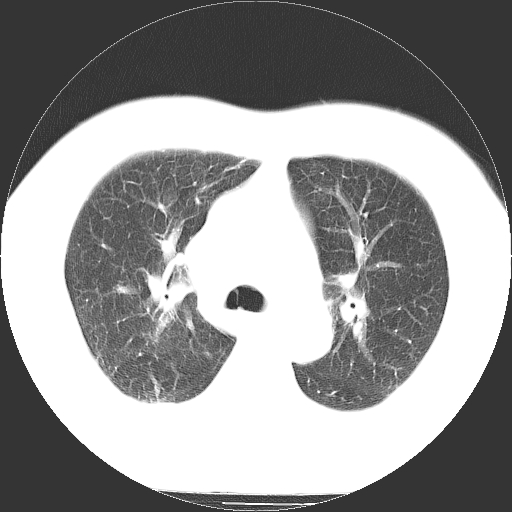

标题: CT21804:男,65岁,咳嗽、咳痰、发热5天。 [打印本页]

男,65岁,咳嗽、咳痰、发热5天。

支气管扩张合并感染,胸膜肥厚

两肺间质纤维化,支扩合并感染,双侧胸腔积液

慢性支气管炎并感染,支扩,双侧少量胸腔积液.